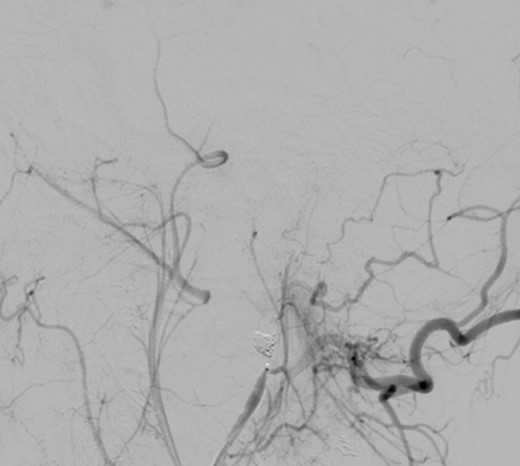

Intraoperative angiography was performed and revealed a PA in relation to the internal maxillary artery, ~1 cm posterior to the left subcondylar region (Fig. 2).

Left common carotid artery angiography in lateral views shows the PA (4.9 × 3 mm).

Under general anaesthesia, the right femoral artery was punctured and a guide catheter (5-Fr) was inserted. Selective runs were performed at the left common carotid artery and external carotid artery. The PA was detected at the bifurcation of superficial temporal artery and internal maxillary artery. Through a selective microcatheterization (1.7-Fr), coiling of the lesion and the bifurcation was performed. The final angiograms showed complete exclusion of the PA after coiling, with collateral flow networks that maintained distal patency of the proximally occluded vessels (Fig. 3).